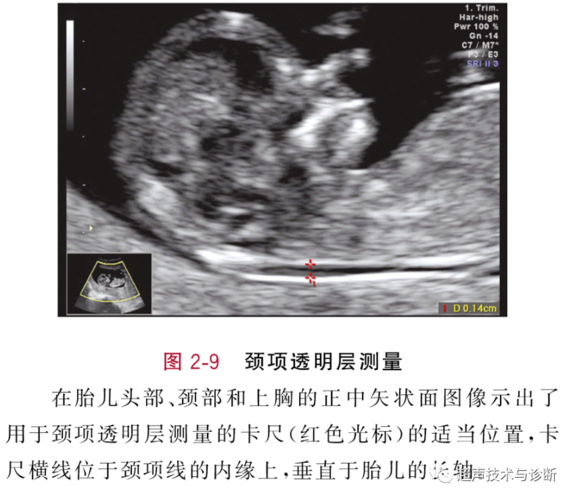

测量时间是11—13 6d周,测量时需遵循以下标准: ①nt的边缘必须